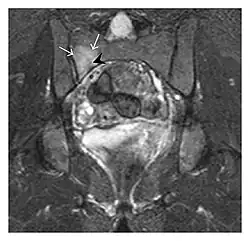

Proximal femoral fractures usually occur in osteoporotic patients, and their signs include subtle neck angulation, trabecular angulation, and subcapital impaction line. A frog-leg lateral view may be helpful if the greater trochanter is short enough. However, positioning can be difficult because of hip pain. In patients with strong suspicion of proximal femoral fracture and negative radiographs, MRI limited to coronal T1 W images and scintigraphy can be highly valuable (Figures 13 and 14). Such an option, with limited examination time, is cost-effective and allows reliable exclusion or confirmation of the diagnosis, preventing an unnecessary stay at the hospital or delayed treatment. Moreover, MRI helps to detect soft tissue abnormalities which are more frequently seen in femoral, acetabular, and pubic injuries than sacral lesions. Concomitant fractures are also frequently seen in typical pelvic sites.[1]

-

a

b

Figure 13: Partial osseous avulsion of the gluteal muscles at the greater trochanter in a 59-year-old man who presented with the right hip pain without a history of trauma. Lauenstein view and anteroposterior and radiographs (not shown) did not show an obvious fracture line or disruption of bony contours in the acetabulum or the right femoral neck. (a) Coronal T1-weighted MRI displays an incomplete fracture line extending partially from the greater trochanter (arrow). (b) Coronal short tau inversion recovery MRI shows heterogeneous hyperintensity in the same region (arrow) as well as hyperintensity within the gluteus medius and minimus muscles (arrowheads) consistent with tissue edema and hematoma.[1]

Figure 14: Subcapital insufficiency fracture in a 55-year-old man with a left hip pain without a history of trauma. Anteroposterior and Lauenstein view radiographs centered on the left hip do not show an obvious fracture line, but mild acetabular osteophytosis was noted consistent with hip osteoarthritis (not shown). (a) Coronal T1-weighted MRI shows a linear low-signal band through the femoral neck corresponding to a fracture line (arrowheads). (b) Bone scintigraphy shows focal uptake (arrow) corresponding to the fracture.[1]